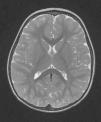

Progresivamente, se observa una mejoría clínica y no presenta nuevos episodios convulsivos, por lo que se remite a domicilio sin tratamiento anticomicial. Se realiza una RM de control a los 2 meses de la crisis, encontrándose el paciente asintomático, constatándose la desaparición de la lesión (fig. 3).

Se han descrito múltiples alteraciones neurológicas en contexto de infección por rotavirus1. Un inusual hallazgo de neuroimagen es la presencia de una lesión transitoria en esplenio del cuerpo calloso que suele desaparecer sin secuelas2,3. Se confirma por lo tanto el primer caso reportado en España sobre esta rara entidad.